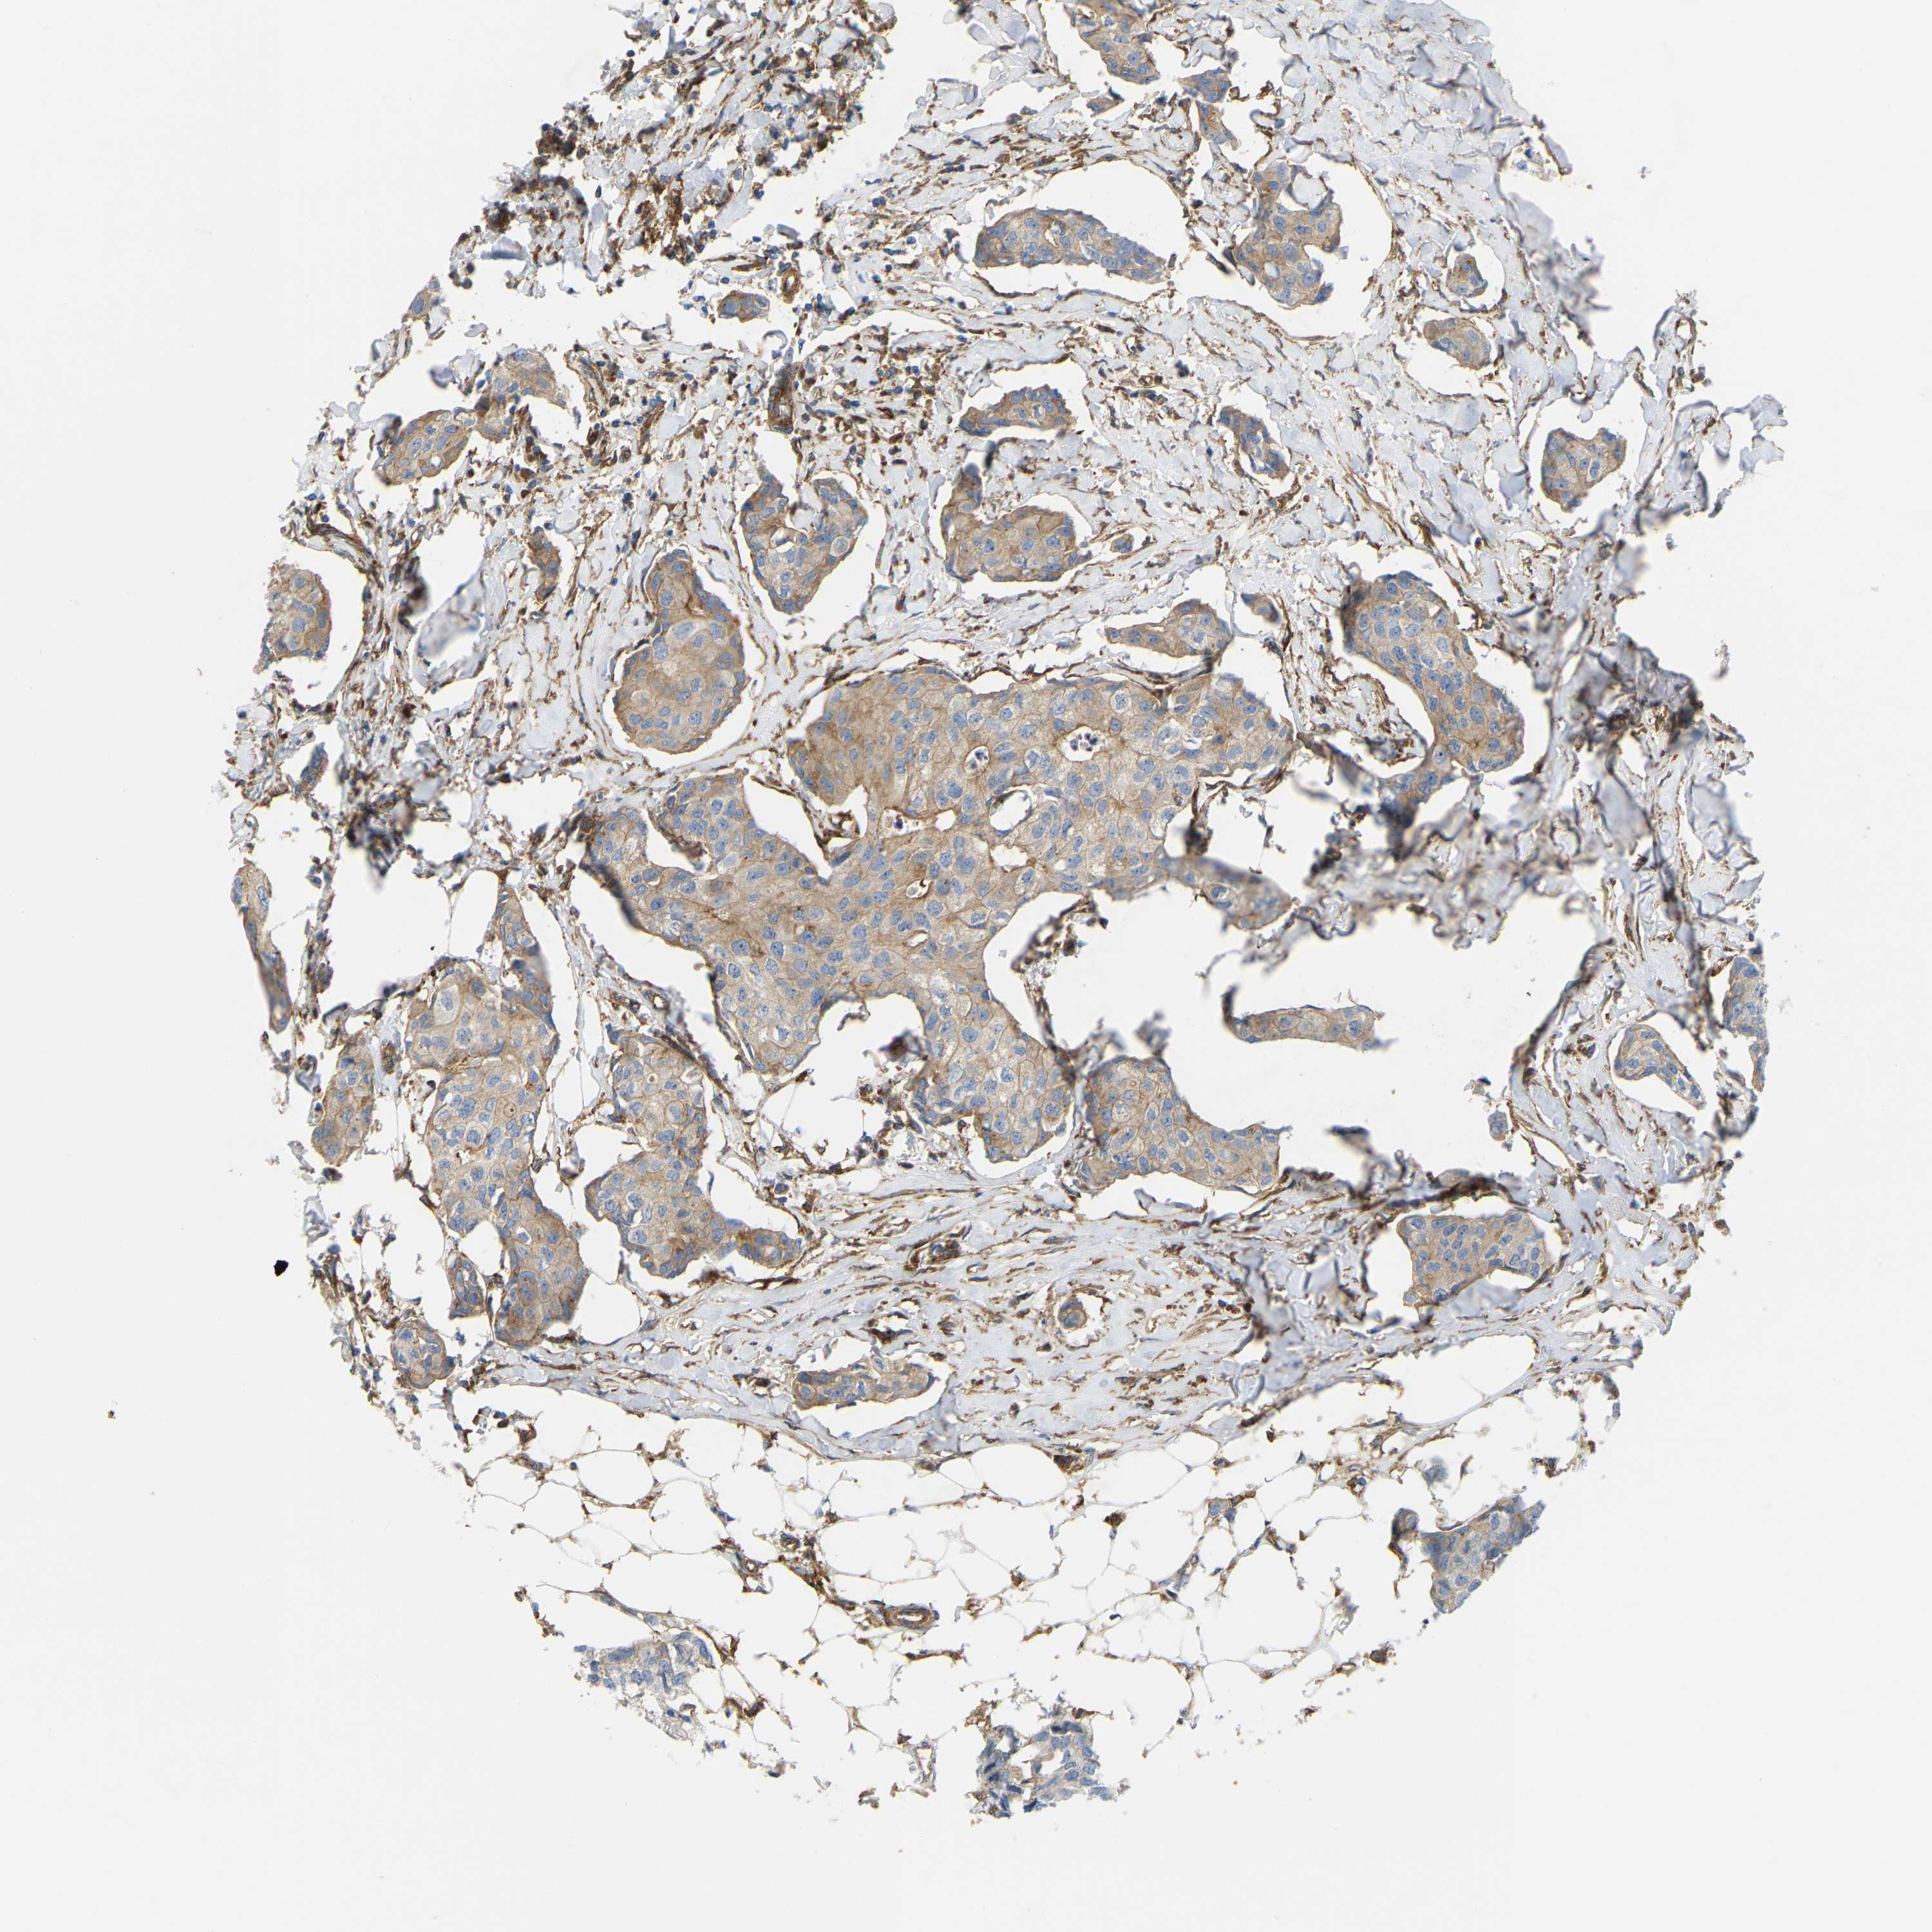

BRCA TCGA BRCA VALIDATION PROTEIN EXPRESSION